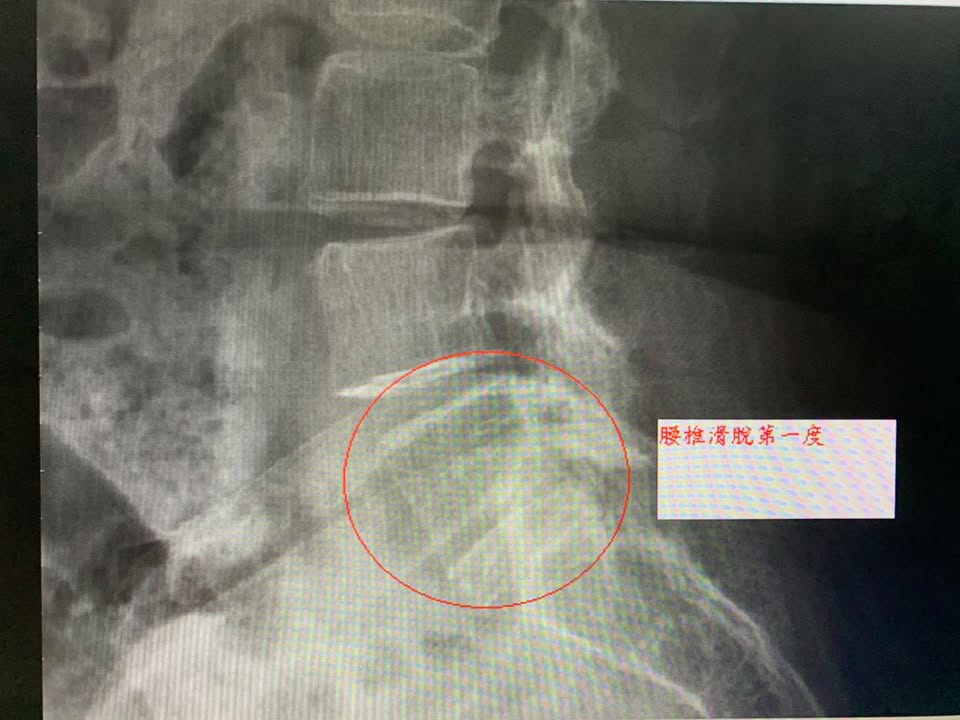

🆘六十多歲的薛伯伯抱怨右腰痛連大腿跟小腿前側快一年多,做過傳統復健,也做過自費的骨震波兩次,,效果還是不如預期,最困擾的症狀還有走路超過二十分鐘就開始痛了,右腰跟髖交會有個點很痛,平常腰就很痠痛,晨起也很痠痛,沒辦法走久,連中午去附近買便當來回走一下路都很痛,x光片顯示腰椎第四椎滑脫第一度合併椎間孔狹窄,經過兒子介紹來接受腰椎整合超微針治療,效果第三次就看到了,至少改善一半,去買便當回來總算輕鬆許多,但是清明節去掃墓走非長久的路忘記休息又小復發,後來聽徐醫師的建議把一個療程八次走完,並且搭配核心肌群復健運動,讓這長達一年多的疼痛夢魘暫時告別了

🔺最主要的原因是脊椎不穩定,導致下背部和臀部的肌肉攣縮疼痛,甚至還會壓迫神經,引起坐骨神經痠、麻、痛的症狀。

▶️常見脊椎滑脫的原因有脊椎退化和椎弓斷裂。 退化性滑脫是因脊椎的退化性關節炎,使得脊椎關節不穩定而滑脫,案例中的薛伯伯就是這種患者;椎弓斷裂性滑脫則可能是先天脊椎間的關節發育不良,或是運動外傷造成椎弓斷裂,通常建議「脊椎滑脫症」患者先復健治療三個月,如果效果不好且大小便失禁或肌肉萎縮則建議開刀